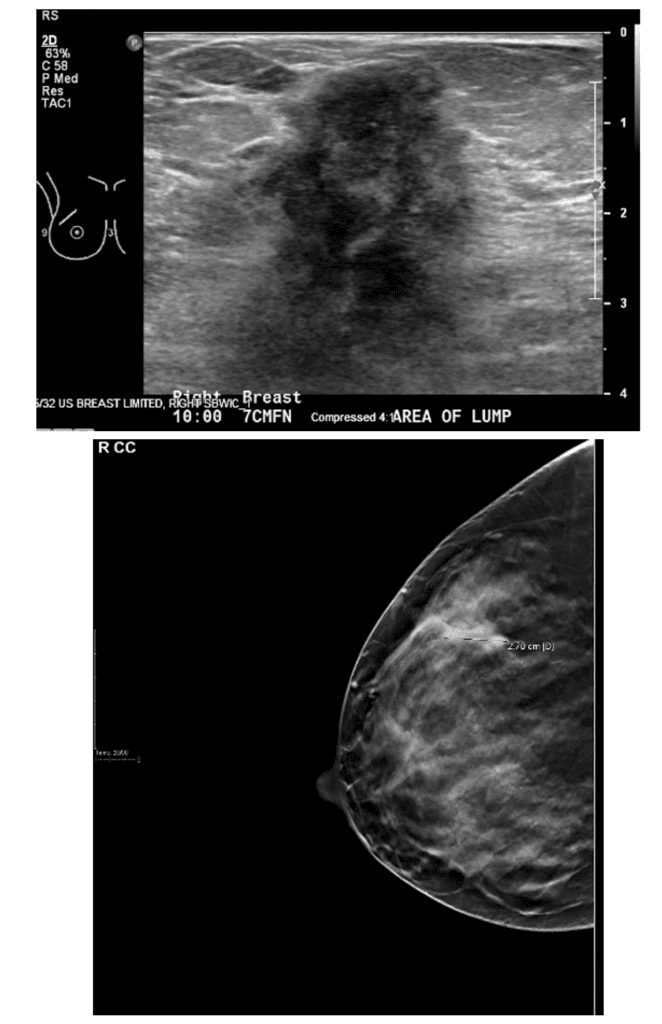

Ultrasound images showing abnormal mass (upper left) and abnormal lymph node (lower left) at patient presentation. After chemotherapy, there was no mass visible in the breast (upper right) and the lymph node had normalized in appearance (lower right).

Chemotherapy prior to breast surgery allows the patient to undergo life-saving treatment first as well as be a candidate for breast conserving surgery after.